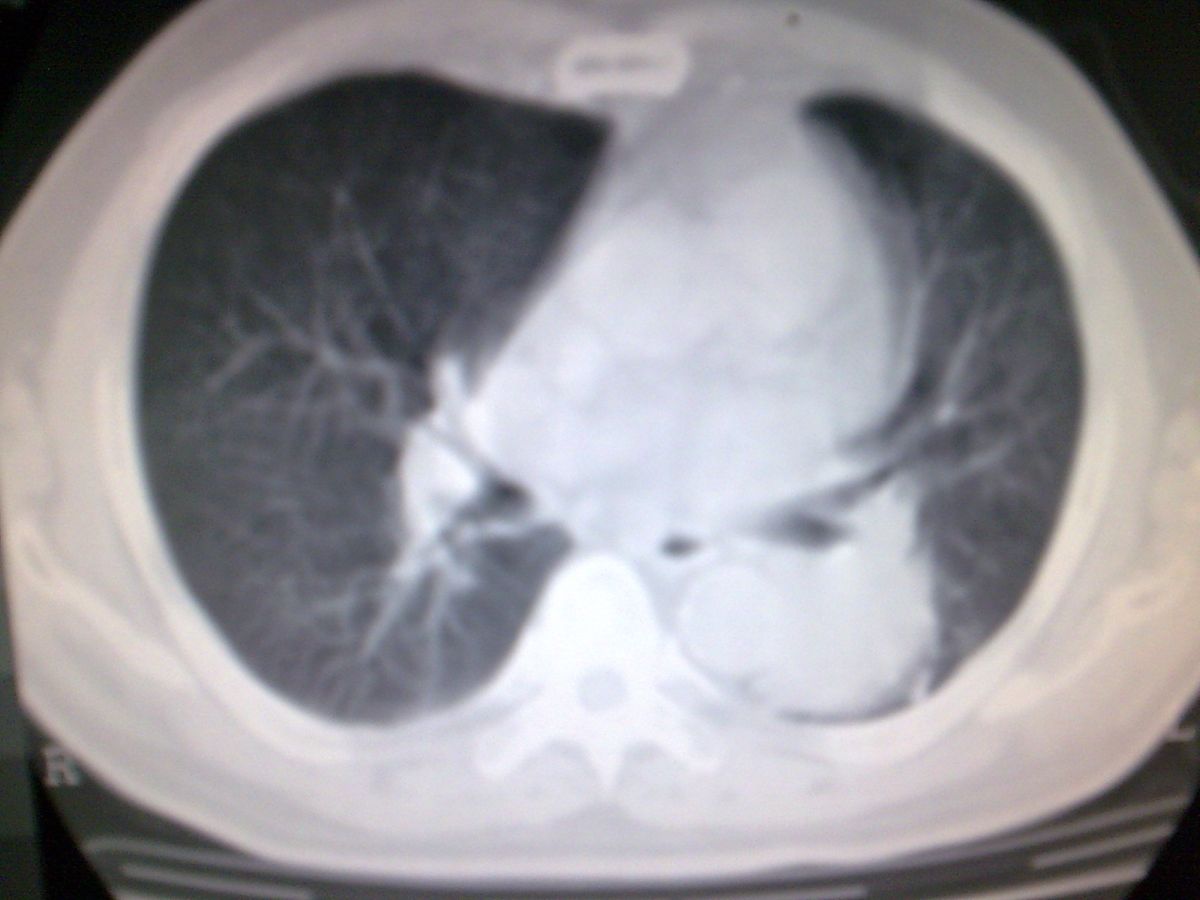

标题: CT19282:男性,70岁,咳血, [打印本页]

标题: CT19282:男性,70岁,咳血,

图片少了些,考虑周围性肺癌

考虑周围性肺癌

周围型肺癌。

考虑左下肺周围性肺癌。

考虑左肺下叶周围型肺癌可能。